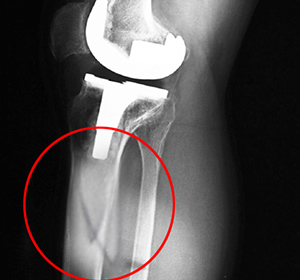

Knee replacement, also called knee arthroplasty, is a surgical procedure in which the worn-out or damaged surfaces of the knee joint are removed and replaced with artificial implants. Any resulting fractures or breaks in the bone around the implant are called periprosthetic knee fractures. These fractures may occur during surgery (intraoperative) or after surgery (postoperative), and usually involve the patella, tibia or the femur (kneecap, shinbone, and thighbone). Women are at higher risk than men.

Diagnosis involves a doctor’s examination followed by injury stabilization to prevent further damage. A traction device is used to keep your leg straight. Your doctor orders an X-ray, MRI or CT scan. Blood tests may also be ordered.

Joint-Revision Surgery: Some cases of periprosthetic knee fracture are caused by a loose implant. Joint-revision involves the removal of the old implant and placement of a new implant with special components to treat the fracture.

Open Reduction and Internal Fixation (ORIF): Some cases of periprosthetic knee fractures do not require replacement of the implant and the fractured bone fragments are fixed together with the help of screws.